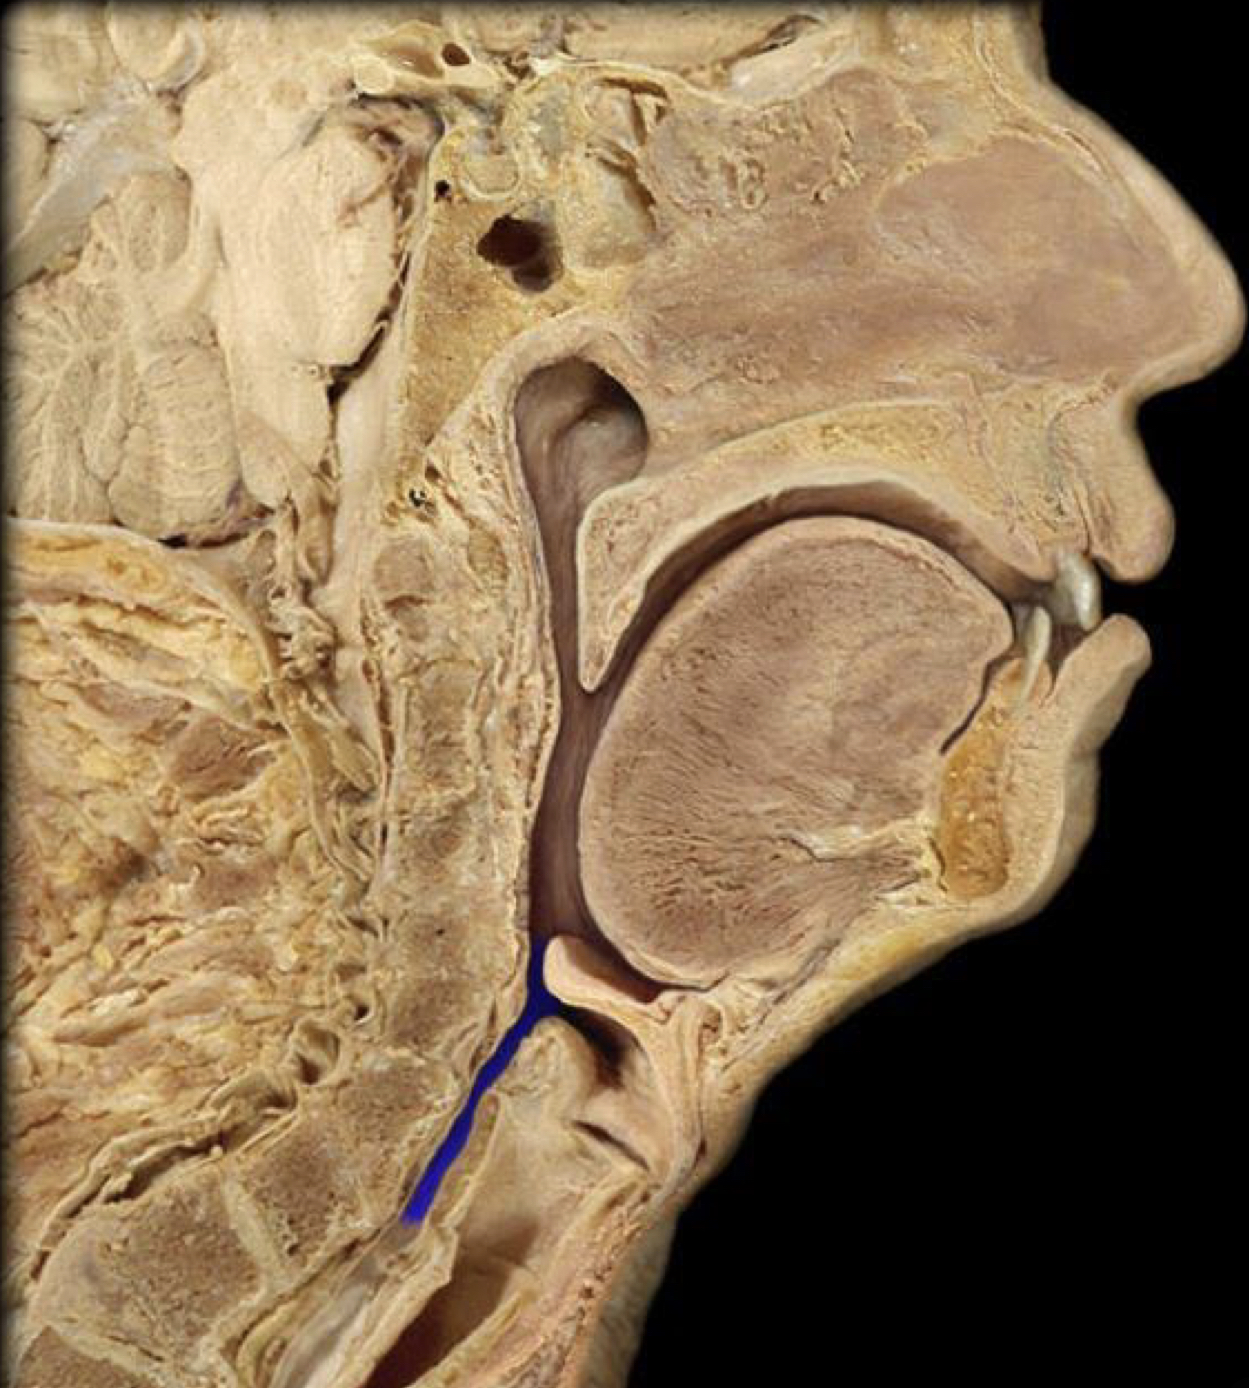

What structure is highlighted in blue?

Trachea (upper respiratory)